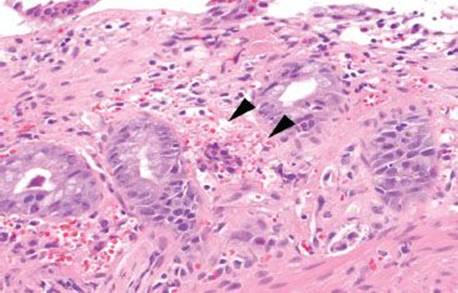

Figure 4.54 Ischemic colitis pattern, withered crypts. Crypt epithelium becomes damaged and sloughs, giving a “withered” appearance to the crypts (arrowheads). Compare these withered crypts to the right side of the photo, which are better preserved.

Decreased blood flow and lack of oxygen to the GI tract result in necrosis or tissue damage, causing ischemia. There are several weak points in the colonic blood supply, known as watershed areas, which result from incomplete anastomosis of the marginal arteries and lack of sufficient collateral circulation. These watershed areas are more vulnerable to ischemic injury than other parts of the colon and include the splenic flexure (or Griffith’s point), the rectosigmoid region at Sudeck’s point, and the ileocecal region. Among the older population, ischemic disease is typically attributable to atherosclerotic mesenteric vascular disease, but the causes of colonic ischemia are many (Table 4.2). The histologic findings are dependent on the timing of the ischemic event (Figs. 4.52–4.63). Early and minimal injury, for example, occurs first as degeneration and sloughing of superficial epithelial cells, edema, and vascular congestion. Later, the epithelial cells become markedly attenuated and the crypts appear compressed and atrophic (“microcrypts”) as the lamina propria swells and hemorrhages. Within 5 hours of total acute vascular occlusion, almost the entire intestinal wall appears necrotic. These changes are devoid of acute inflammation until reperfusion occurs. Paradoxically, reperfusion further injures the tissues by introducing oxygen free radical formation,16 the severity of which is dependent on the duration of the preceding hypoxia.